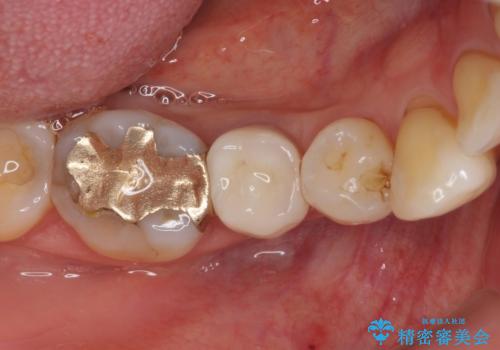

歯に穴があいた 奥歯のセラミック治療

- メインテナンスの際、以前よりものが挟まることが気になっていた患者様です。

神経が取り除かれた歯であるため、虫歯で歯が失われていく際に痛みを伴わなず、気がついたら大きな穴があいていました。

虫歯を全て除去したうえで新しい土台を築製し、セラミッククラウンにより補綴治療を行うこととしました。